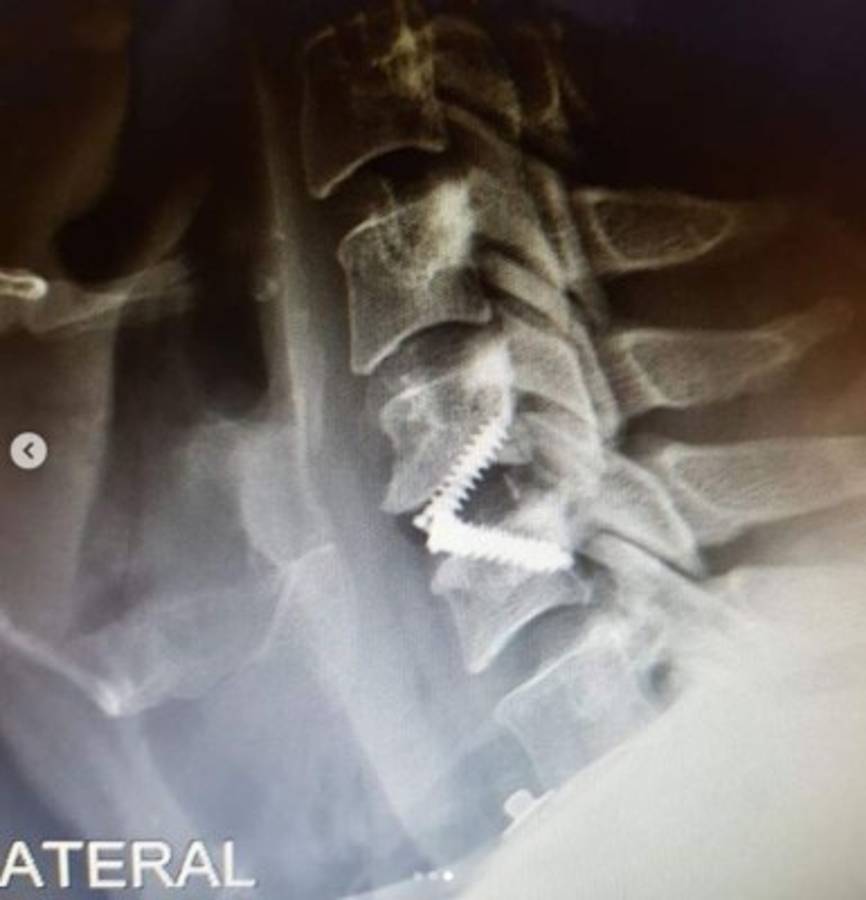

CIUDAD DE MÉXICO, MÉXICO.- El actor mexicano Arath de la Torre fue sometido recientemente a una cirugía de emergencia. A través de sus redes sociales informó a sus seguidores que fue operado de una hernia de disco cervical que lo hizo enfrentar terribles dolencias durante años.

'Fui intervenido de una hernia de disco cervical, estoy en perfectas condiciones, a pesar de haber sido un accidente (caída), fue programada para el 26 de septiembre para poder darle colchón a 'Mi marido tiene más familia' y cumplir con otros compromisos laborales. Esta es la verdad y no se dejen llevar. Estaré de regreso en la telenovela en dos semanas y no salgo de la misma. Gracias a mi Neurocirujano y a todo su equipo. Viva la vida', escribió en Instagram.

Así mostró su operación a los seguidores de Instagram. Foto @arathdelatorre